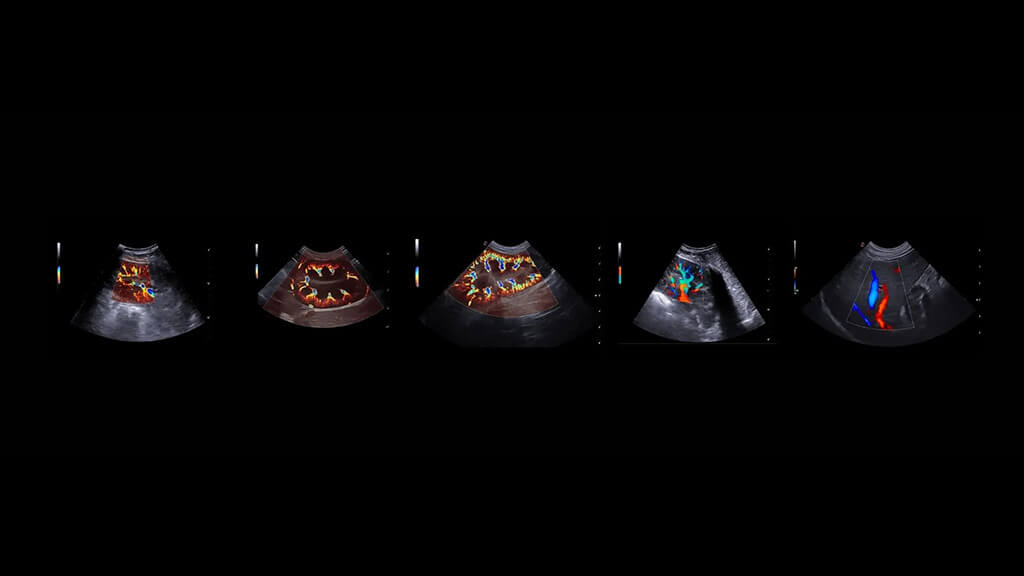

Ekokardiyografi (EKO), veteriner hekimlikte kalp hastalıklarının tanısı, derecelendirilmesi ve takibinde kullanılan en değerli görüntüleme yöntemlerinden biridir. Yüksek frekanslı ses dalgaları ile kalbin kapaklarını, odacıklarını, kas yapısını ve kan akımını gerçek zamanlı değerlendirmeye olanak sağlar.

Kalp hastalıklarında yalnızca “var/yok” yanıtı değil; hastalığın şiddeti, kalbin çalışma performansı ve ilerleyişi hakkında sayısal ve klinik olarak kritik bilgiler sunar. Bu nedenle birçok kardiyovasküler problemde EKO, tanısal yaklaşımın temel basamağıdır.